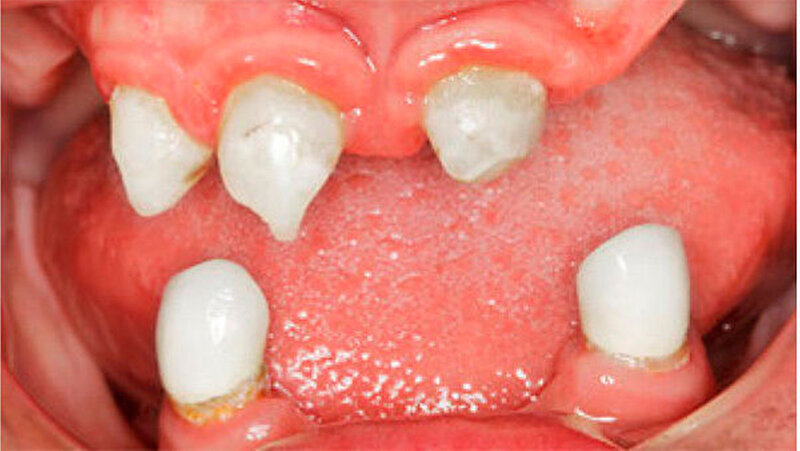

Der bei Behandlungsbeginn 14-jährige Patient war mit einer neun beziehungsweise fünfjährigen Prothese im Unter- beziehungsweise Oberkiefer versorgt (Abb. 2 und 3). Die angelegten Zapfenzähne 12, 11 und 21 waren bereits mehrfach konservierend restauriert und wiesen diverse Stellen mit Sekundärkaries auf. Die Kronenränder der Zähne 33 und 43 waren deutlich sondierbar. Der Kieferkamm im Unterkiefer war aufgrund der fehlenden Zahnanlagen sehr schmal (Abb. 4 bis 6). Die Panoramaschichtaufnahme zeigte das reduzierte vertikale Knochenangebot (Abb. 7). Da die Vitalerhaltung der wenigen Restzähne aufgrund des jungen Alters des Patienten unbedingt anzustreben war, wurde als Behandlungsziel im Ober- und Unterkiefer eine Versorgung mit Hybridprothesen, retiniert auf Teleskopkronen, festgelegt.

Bei dieser bei Behandlungsbeginn 16-jährigen Patientin waren seit Geburt nur die beiden ersten Molaren im Oberkiefer ausgebildet. Die Folge waren schmale und niedrige Alveolarkämme mit einem flachen Gaumengewölbe (Abb. 16 und 17). Die röntgenologische Abbildung bestätigte das geringe vertikale Knochenangebot. Eine Formanomalie der Zahnwurzeln ließ auf taurodonte Molaren schließen. Beide Molaren wiesen ausgedehnte kariöse Läsionen auf (Abb. 18).